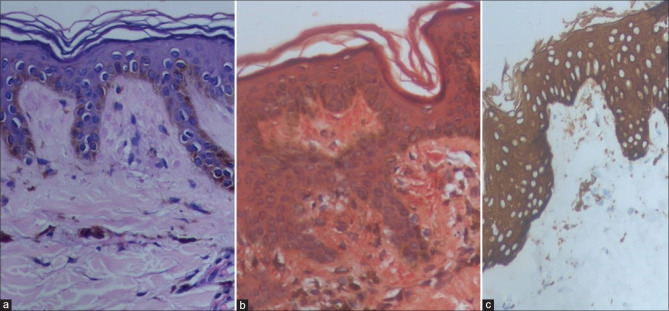

Familial Primary Cutaneous Amyloidosis Across Generations.